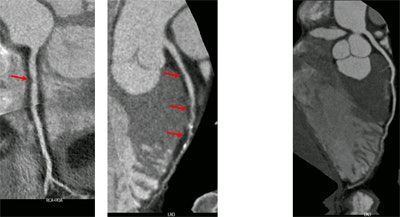

In total, 314 individuals older than 45 underwent prospective ECG-triggered CT using a 256-slice CT scanner (Brilliance iCT, Philips Healthcare). The presence of relevant coronary artery disease (CAD) was defined as having an Agatston calcium score of at least 100 on noncontrast CT or obstructive (≥ 50%) luminal stenosis on coronary CT angiography.

All 314 participants had good exercise tolerance with no signs of ischemia on ECG, and 51 (16%) had coronary calcium scores greater than 100. Coronary CT angiography added eight more at-risk patients with luminal narrowing greater than 50%.

Altogether, CT identified CAD in 59 (19%) of the 314 participants (95% confidence interval: 15%-24%). Seventeen patients (5%) had moderate-to-severe coronary stenosis of at least 50%.